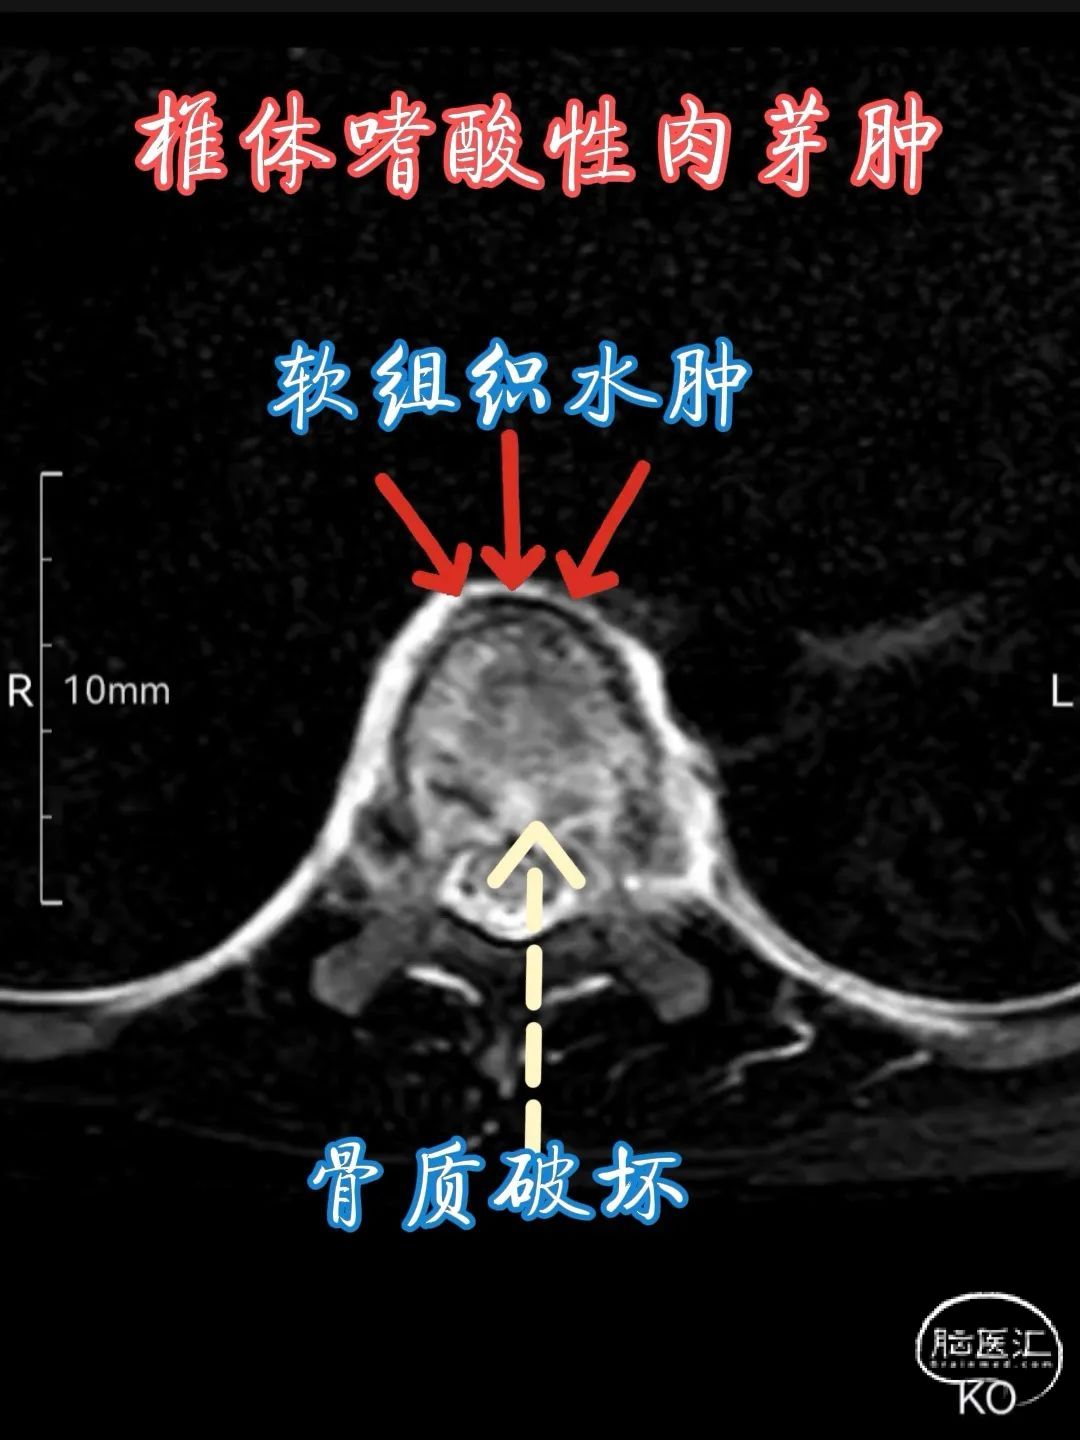

•CT 检查 :CT 扫描能更清晰地显示病变的范围和细节,对于发现早期、较小的病变以及评估椎体破坏的程度具有优势。在 CT 图像上,病变通常呈低密度影,边界较清楚,增强扫描后可有不同程度的强化,强化程度与病变的血管化程度及细胞密度有关。同时,CT 还可显示病变对周围结构的侵犯情况,如椎弓根、椎管、椎旁软组织等,有助于术前评估和制定治疗方案。

•MRI 检查 :MRI 对于检测椎体嗜酸性肉芽肿具有较高的敏感性,能够清晰地显示病变的范围、部位、形态以及与周围组织的关系。在 T1 加权像上,病变通常呈低到中等信号强度,与正常骨髓相比信号较低;在 T2 加权像上则呈高信号强度,这是由于病变组织内含有较多的水分和黏多糖等成分。此外,MRI 还可显示病变周围的软组织水肿、炎症反应以及神经受压等情况,对于判断病情和制定治疗计划具有重要价值。